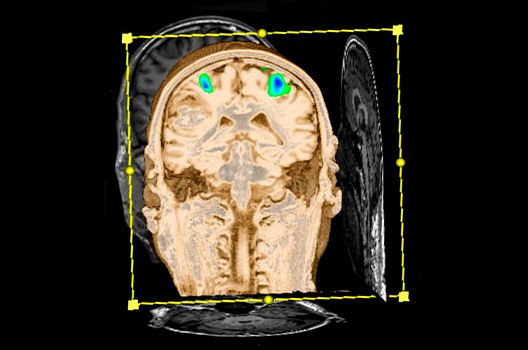

- Funktionelle Bildgebung des Gehirns (fMRT)

Die Schwerpunkte in der MR-Forschung liegen in der multiparametrischen und funktionellen Bildgebung bei onkologischen und anderen, neuroradiologischen Fragestellungen und umfassen die Anwendung modernster MR-Verfahren sowie die Untersuchung an Hochfeld-Geräten.

Die Magnetresonanztomographie (MRT) ist ein Verfahren, bei dem durch magnetische Kräfte Bilder des Körperinneren angefertigt werden. In der Neuroradiologie können manchmal kleinste Veränderungen schwere Folgen haben; daher forschen wir an der Entwicklung hochauflösender MRT-Sequenzen, mit denen diese Prozesse und auch einzelne Nervenfaserbahnen sichtbar gemacht werden können. Darüber hinaus sind bei vielen Erkrankungen des Gehirns die Blutgefäße betroffen. Daher arbeiten wir an der Neu- und Weiterentwicklung von MRT-Sequenzen zur Darstellung der Blutgefäße und zur Blutflussanalyse (sog. „Angio-MRT“). Einen besonderen Forschungsschwerpunkt unserer Klinik stellen die MR-Protonenspektroskopie und die funktionelle MRT dar, mit denen die Analyse einzelner chemischer Substanzen im Hirngewebe oder die Darstellung ausgewählter Hirnfunktionen möglich ist.